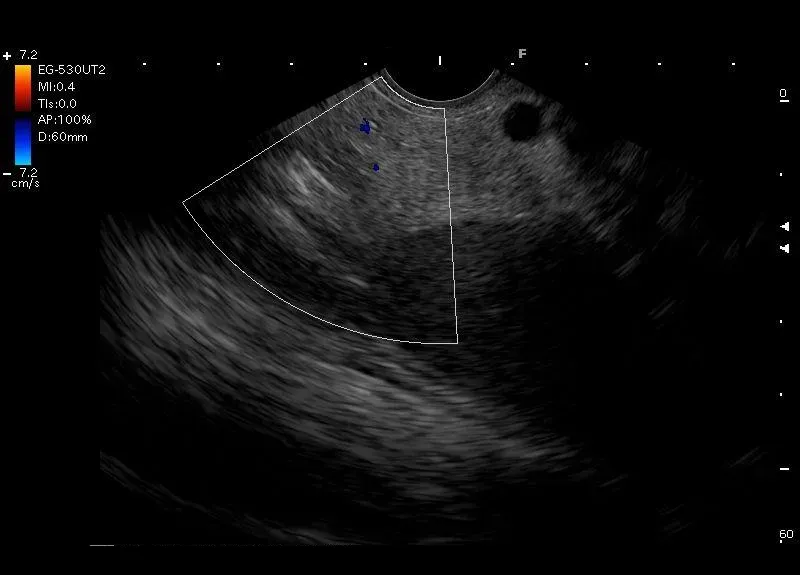

Zobrazowana przez głowice EUS położoną w żołądku, położona obok ogona trzustki - śledziona